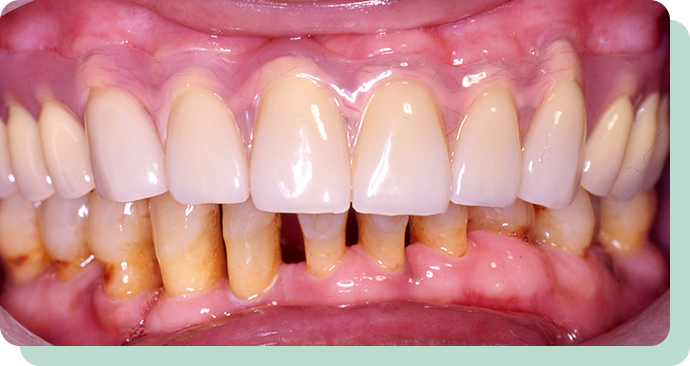

処置前後

左の写真は、歯周病が進んで、どんどん歯が抜けていっている状態です。

この方は、歯を短くし、金属のキャップの上に特殊な入れ歯を装着。

これにより、快適にお食事ができるようになりました。

リスク:疼痛・咬合時痛・冷水痛・出血・歯ぐきへの損傷

費用:金属床義歯使用 280,000円